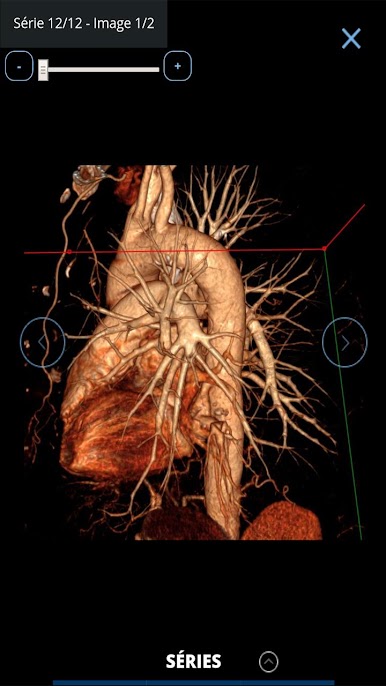

The largest French bank of clinical cases of medical imaging and radiology in your pocket!

Consultation with images of hundreds of typical and rare cases is simple, all accompanied by explanatory captions and course records. All imaging modalities are represented: CT, MRI, ultrasound, PET-CT scans, interventional radiology angiography.